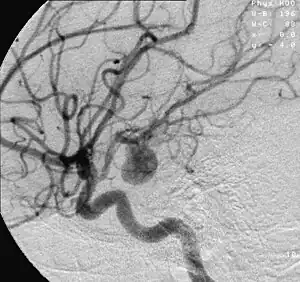

- Focal cerebral ischemia – A stroke occurring in a localized area that can either be acute or transient. This may be due to a variety of medical conditions such as an aneurysm that causes a hemorrhagic stroke, or an occlusion occurring in the affected blood vessels due to a thrombus (thrombotic stroke) or embolus (embolic stroke).[21] Focal cerebral ischemia constitutes a large majority of the clinical cases in stroke pathology with the infarct usually occurring in the middle cerebral artery (MCA).[22]

- Ischemic hypoxia ( or "stagnant hypoxia") – Reduced brain oxygen is caused by inadequate blood flow to the brain. Stroke, shock, cardiac arrest and heart attack may cause stagnant hypoxia. Ischemic hypoxia can also be created by pressure on the brain. Cerebral edema, brain hemorrhages and hydrocephalus exert pressure on brain tissue and impede their absorption of oxygen.